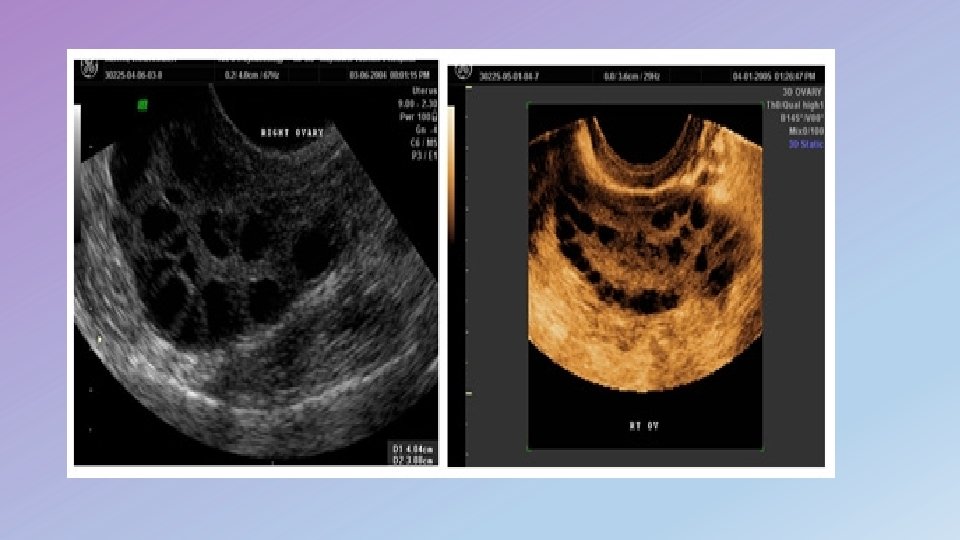

Ultra Sound Findings two criteria on the basis of which a polycystic ovary may be identified: • ovarian volume • number of follicles polycystic ovaries are present when : (a) one or both ovaries demonstrate 12 or more follicles measuring 2– 9 mm in diameter. (b) the ovarian volume exceeds 10 cm 3. Only one ovary meeting either of these criteria is sufficient to establish the presence of polycystic ovaries

Number of Follicles : • data suggested that 12 or more follicles 2– 9 mm in size per ovary provided the best threshold for the diagnosis of PCOS • polycystic ovary as one that contains (in one plane) at least 10 follicles arranged peripherally around an echodense stroma.

Transverse US image of the right ovary demonstrates the classic “string of pearls” appearance of a polycystic ovary. This subjective appearance should not be used in place of ovarian volume and follicle count to identify a polycystic ovary, according to the Rotterdam definition.

Selected images from a three-dimensional US examination of the right ovary demonstrate determination of the number of follicles present (follicles numbered 1– 41) across the entire volume of the ovary, according to the Rotterdam definition.